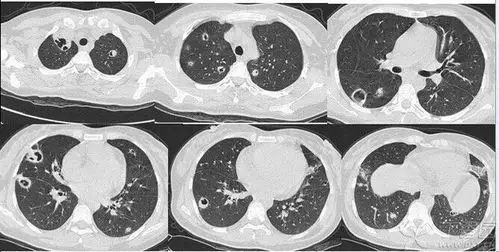

几组肺炎ct读片大畅带你来看图